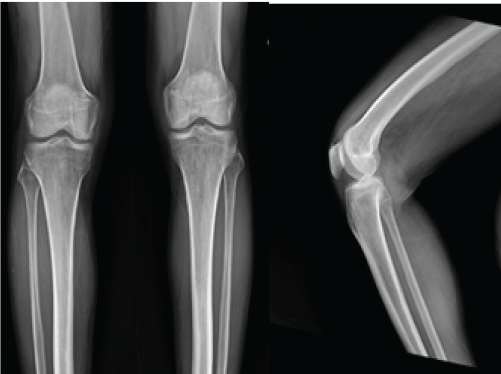

Mucoid Degeneration of Posterior Cruciate Ligament – A Case Study

Amit Kumar Jha , Ankit Chaubey , Swaroop Patel , Santosh Kumar Singh , Amit Singh ………………………………p.153-156